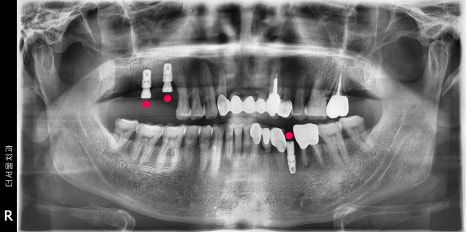

1) #17번 치아 결손

2) 소구치 잔존 치근만 남아있기에 발치 결정

3) apex lesion (뿌리 염증) 에 따라 발치 결정

4) proximal caries (사이충치)에 따라 신경치료

이렇게 4가지의 특이소견이 관찰 되었었습니다.

좌 : 1차 op, 우 : 2차 op 및 final

미리 결과를 예측했으니, 엑스레이에서

볼 수 있는 것 처럼 네비게이션 임플란트 3개를

심는데는 15분 채 걸리지 않습니다.